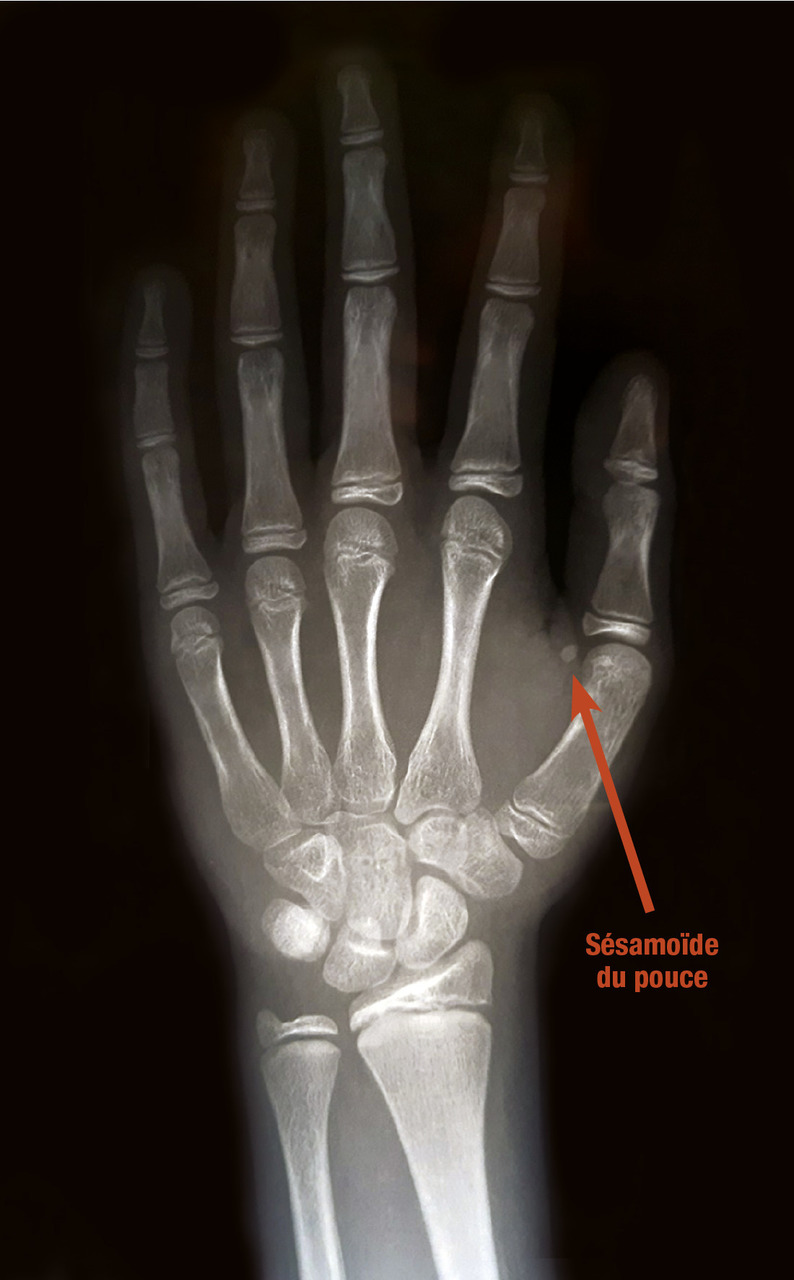

Détermination de l’âge osseux (fig. 4)

Elle permet d’obtenir un repère quantifiable de la maturation du squelette par les stéroïdes sexuels. Il est lu à l’aide d’un atlas radiologique (Greulich et Pyle), à partir d’une radiographie du poignet et de la main gauche. Le début de la puberté correspond habituellement à un âge osseux de 13 ans chez le garçon et de 11 ans chez la fille. Cet âge osseux correspond grossièrement à l’apparition du sésamoïde du pouce.

La détermination de l’âge osseux permet d’obtenir un repère quantifiable de la maturation du squelette par les stéroïdes sexuels. Il est lu à l’aide d’un atlas radiologique (Greulich et Pyle), à partir d’une radiographie du poignet et de la main gauche. Le début de la puberté correspond habituellement à un âge osseux de 13 ans chez le garçon et de 11 ans chez la fille. Cet âge osseux correspond grossièrement à l’apparition du sésamoïde du pouce. L’accélération de la maturation osseuse est la conséquence de la sécrétion des stéroïdes sexuels. Elle signe le risque de la survenue d’une puberté précoce, la soudure prématurée des cartilages de croissance entraînant un risque de petite taille définitive.